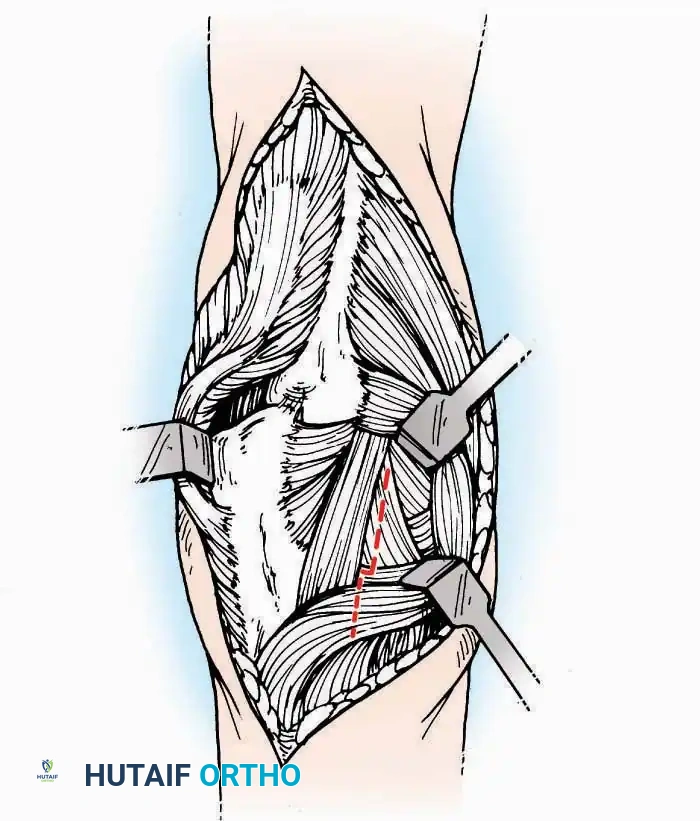

Medial Approach

Indications: Fixation of sustentaculum tali fractures, medial process fractures, or excision of medial tarsal coalitions.

Positioning: Supine with the hip externally rotated and knee flexed (figure-of-four position).

Surgical Technique:

* Incision: Begin 2.5 cm anterior and 4 cm inferior to the medial malleolus. Carry it posteriorly along the medial surface of the foot toward the Achilles tendon.

* Superficial Dissection: Divide the fat and fascia to define the inferior margin of the abductor hallucis muscle.

* Deep Dissection: Mobilize the abductor hallucis muscle belly and retract it dorsally to expose the medial and inferomedial aspects of the calcaneal body.

* Plantar Exposure: Continue distally by dividing the plantar aponeurosis and the muscular attachments to the calcaneus, or strip them subperiosteally with an osteotome.

* Neurovascular Warning: Meticulously identify and protect the medial calcaneal nerve and the nerve to the abductor digiti minimi (first branch of the lateral plantar nerve), which are highly vulnerable during inferior retraction.